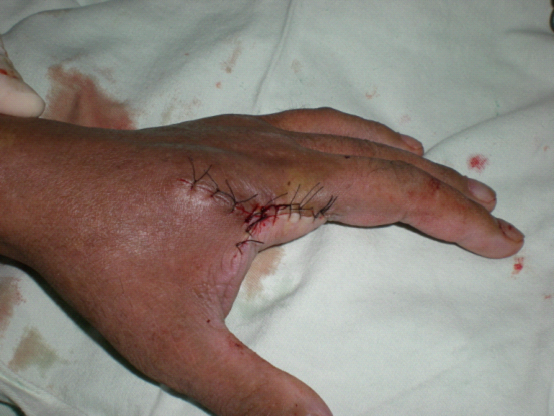

王某某,男,54岁,左示指近节指骨骨折在外院行切开复位钢板骨折内固定术,术后刀口感染,在外治疗一年余,无好转,来我院诊断为慢性骨髓炎,患者强烈要求截指。

治疗前